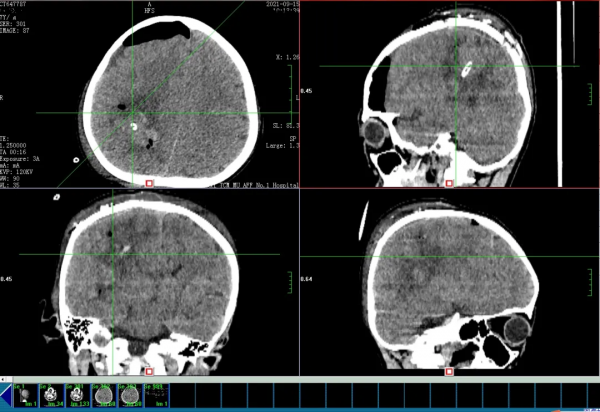

經過檢查,神經外科周海靜主治醫生告訴老師和匆忙趕來的媽媽——孩子得了腦出血!而且出血量特別大,約98ml!

術中迅速在患兒右側頂葉腦實質內鎖定了出血灶,在顯微鏡輔助下精心操作乾淨徹底的清除了血腫並且最大限度避免了手術對腦組織的損傷。腦組織張力隨著血腫清除逐漸下降,這意味著顱內壓力下降,腦疝危機逐步解除,手術目的已經達到。

然而經驗豐富的陳銳心情卻沒能放鬆下來,因為他發現了空了的血腫腔內顯出一團畸形的血管團。

腦動靜脈畸形是一種先天性局部發育異常的血管團,動靜脈之間不經過毛細血管網連通。血液直接從動脈系統流入壓力相對較低的靜脈系統,常引起頭痛、癲癇以及顱內出血。這就是患兒腦出血的責任病灶。

出血原因找到了,但是此處血管異常複雜,正常供血動脈和畸形血管團混雜不清,肉眼難以分辨,此時貿然切除畸形血管團,很可能會誤傷正常血管,而且病灶位於腦重要功能區,強行從腦組織中將其剝離切除必然損傷周圍尚有功能的腦組織,加重病情。